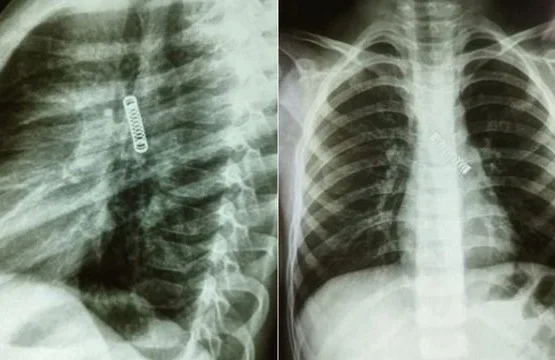

VIDEO/ Atentat me 9 plumba, dalin pamjet e ekzekutimit të shqiptarit në Ekuador

Shqiptari Arjan Rizaj është ekzekutuar me armë në Guayaquil të Ekuadorit. Sipas mediave, ngjarja ka ndodhur më 9 nëntor rreth